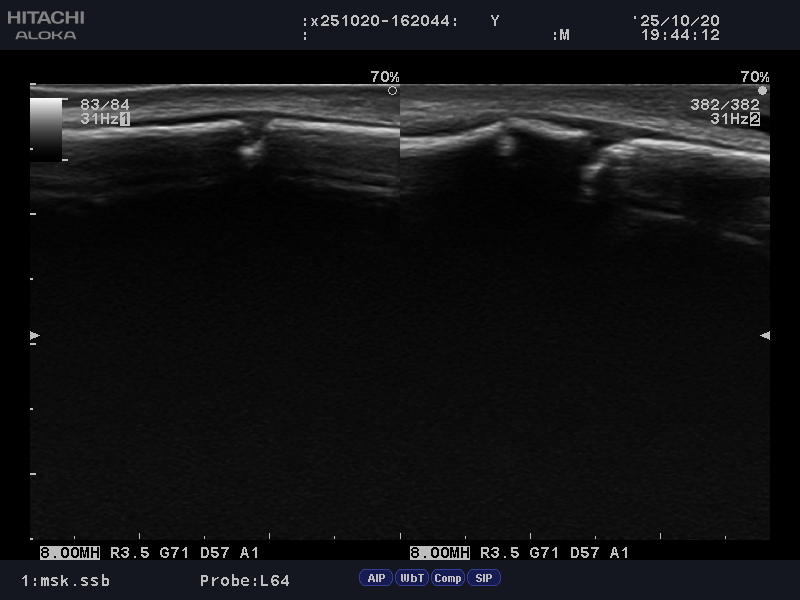

超音波検査では下記の様な像が見られました

骨折を伴う骨端線損傷と判断し